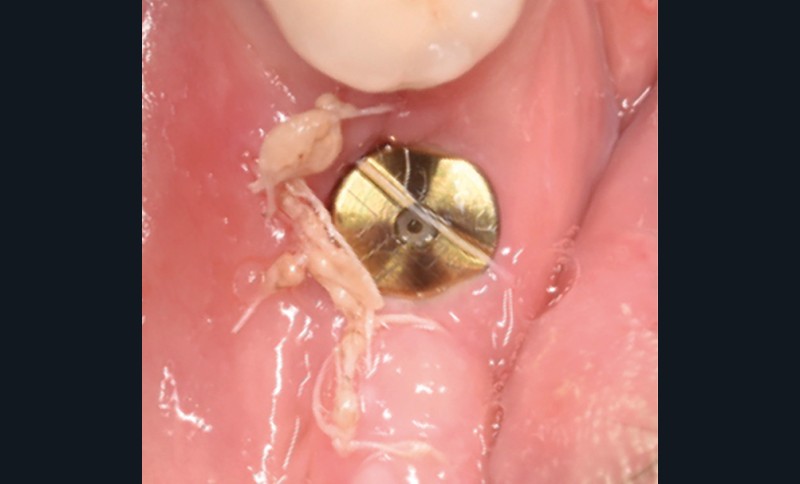

La patiente est restée 4 semaines sans couronne. Après l’intervention chirurgicale, elle a entamé un programme de soins péri-implantaires et parodontaux, avec des visites de rappel tous les 4 mois.

Dans les cas de traitement de péri-implantite, un suivi d’un an est considéré comme un suivi court. Néanmoins, le cas présent est stable après un an et ne présente aucun signe de récidive. Des contrôles supplémentaires sont nécessaires.